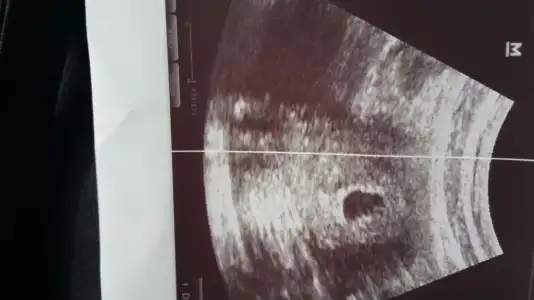

ben ilk gebeliğimde 5+1 de gitmiştim net görmüştük bakalım bunda da azıcık geçsin önümüzdeki hafta gideyim diyorum cuma günü gelicek buraya doktor olmazsa bi gider görünürümAlttan bakmıyorlar zaten cnm bol su iç gitmeden idrara sıkışık git daha iyi gorunur

ben ilk gebeliğimde 5+1 de gitmiştim net görmüştük bakalım bunda da azıcık geçsin önümüzdeki hafta gideyim diyorum cuma günü gelicek buraya doktor olmazsa bi gider görünürüm